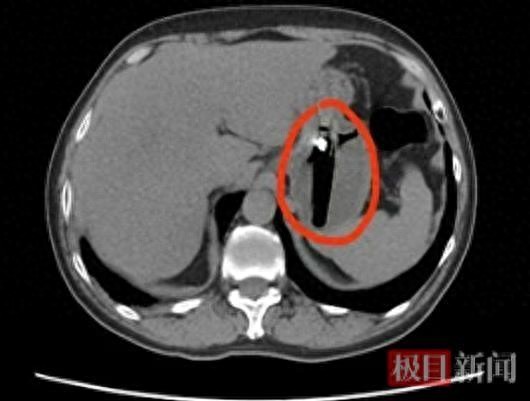

一拍急诊胸腹部CT,真相大白:胃里赫然躺着一个长约8厘米的异物!普外科二病区的接诊医生郭敦伟拿着片子,反复追问陈先生最近的饮酒经历,这才推断出罪魁祸首就是那个被误吞的打火机。医生解释,人喝醉了,咽喉神经反应迟钝,食管肌肉松弛,异物很容易"长驱直入"滑进胃里。这打火机个头太大,过不了幽门排不出去,就在胃里跟着蠕动瞎折腾,把胃壁磨得不轻。更要命的是,胃酸像水滴石穿一样持续腐蚀,打火机外壳一旦破损,里面的易燃气体漏出来会中毒,甚至可能穿透胃壁造成穿孔、腹膜炎,到时候可是要命的。